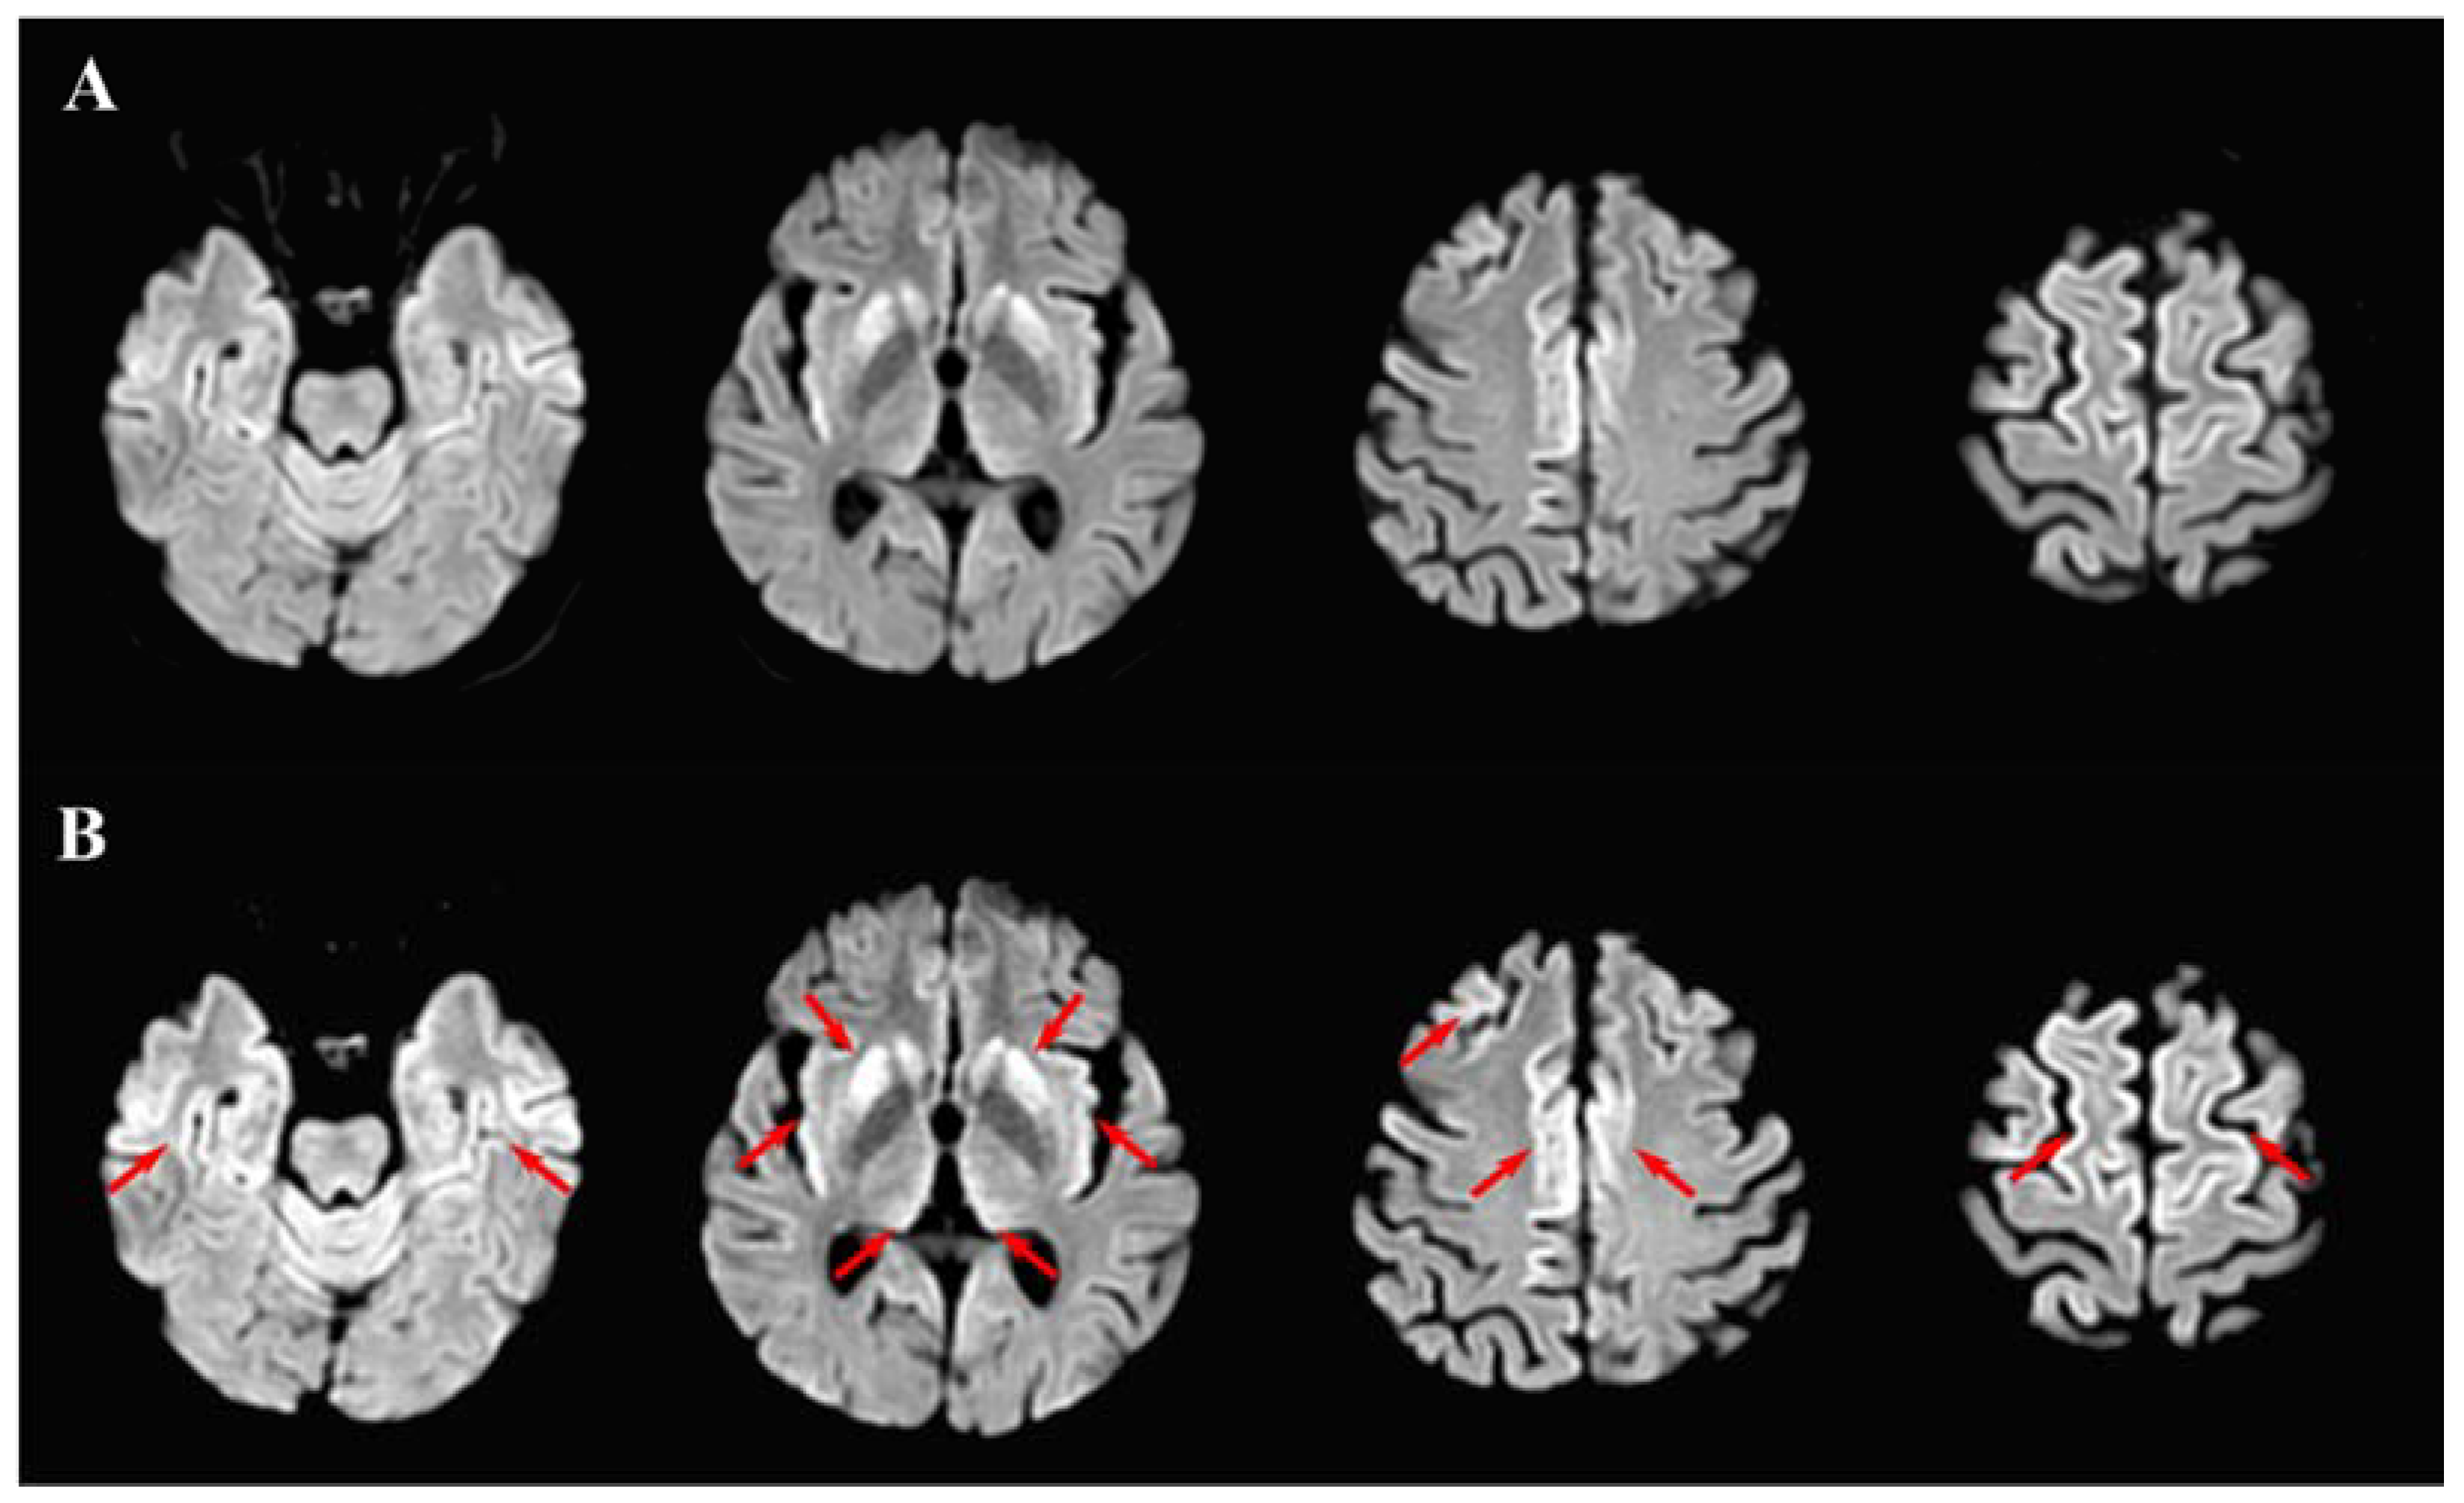

2. Case Report